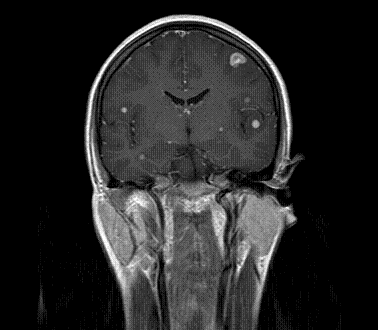

以下是引用xly在2009-5-20 11:38:00的发言:[br]大脑、小脑及脑干多发结节状及环状稍长t1、长t2异常信号影,部份病灶中心见稍短t1、短t2信号,病灶边缘光滑、边界清楚,灶周环状水肿,dwi为低信号,增强扫描上述病灶均匀强化,部份病灶中心无强化,脑膜小结节异常强化,考虑脑膜脑结核可能性大。胸片如何?ppd如何?期待结果。